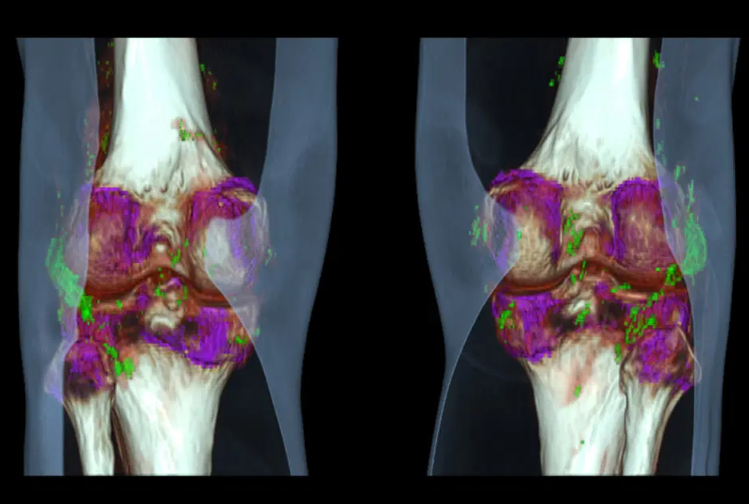

Os sistemas de Dupla Energia podem usar dois tubos de raio-X diferentes ou alternância rápida da voltagem em um único tubo. As imagens adquiridas em diferentes níveis energéticos são combinadas por softwares específicos, gerando mapas espectrais e imagens com realce seletivo de tecidos e elementos como cálcio, urato e iodo.

- Gota: identificação de cristais de urato monosódico;

- Ortopedia: separação entre tecido ósseo e partes moles com alta precisão.